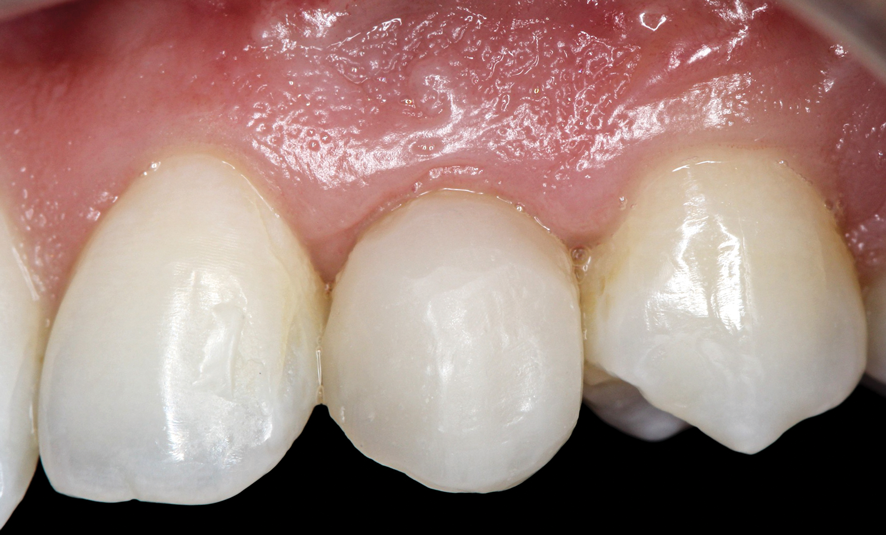

(33.) Retracted view with the teeth apart and close-up view of the definitive screw-retained zirconia restoration in position (Definitive restoration fabricated by Sam Alawie and Beverly Hills Dental Lab).

Figure 33

(34.) Retracted view with the teeth apart and close-up view of the definitive screw-retained zirconia restoration in position (Definitive restoration fabricated by Sam Alawie and Beverly Hills Dental Lab).

Figure 34